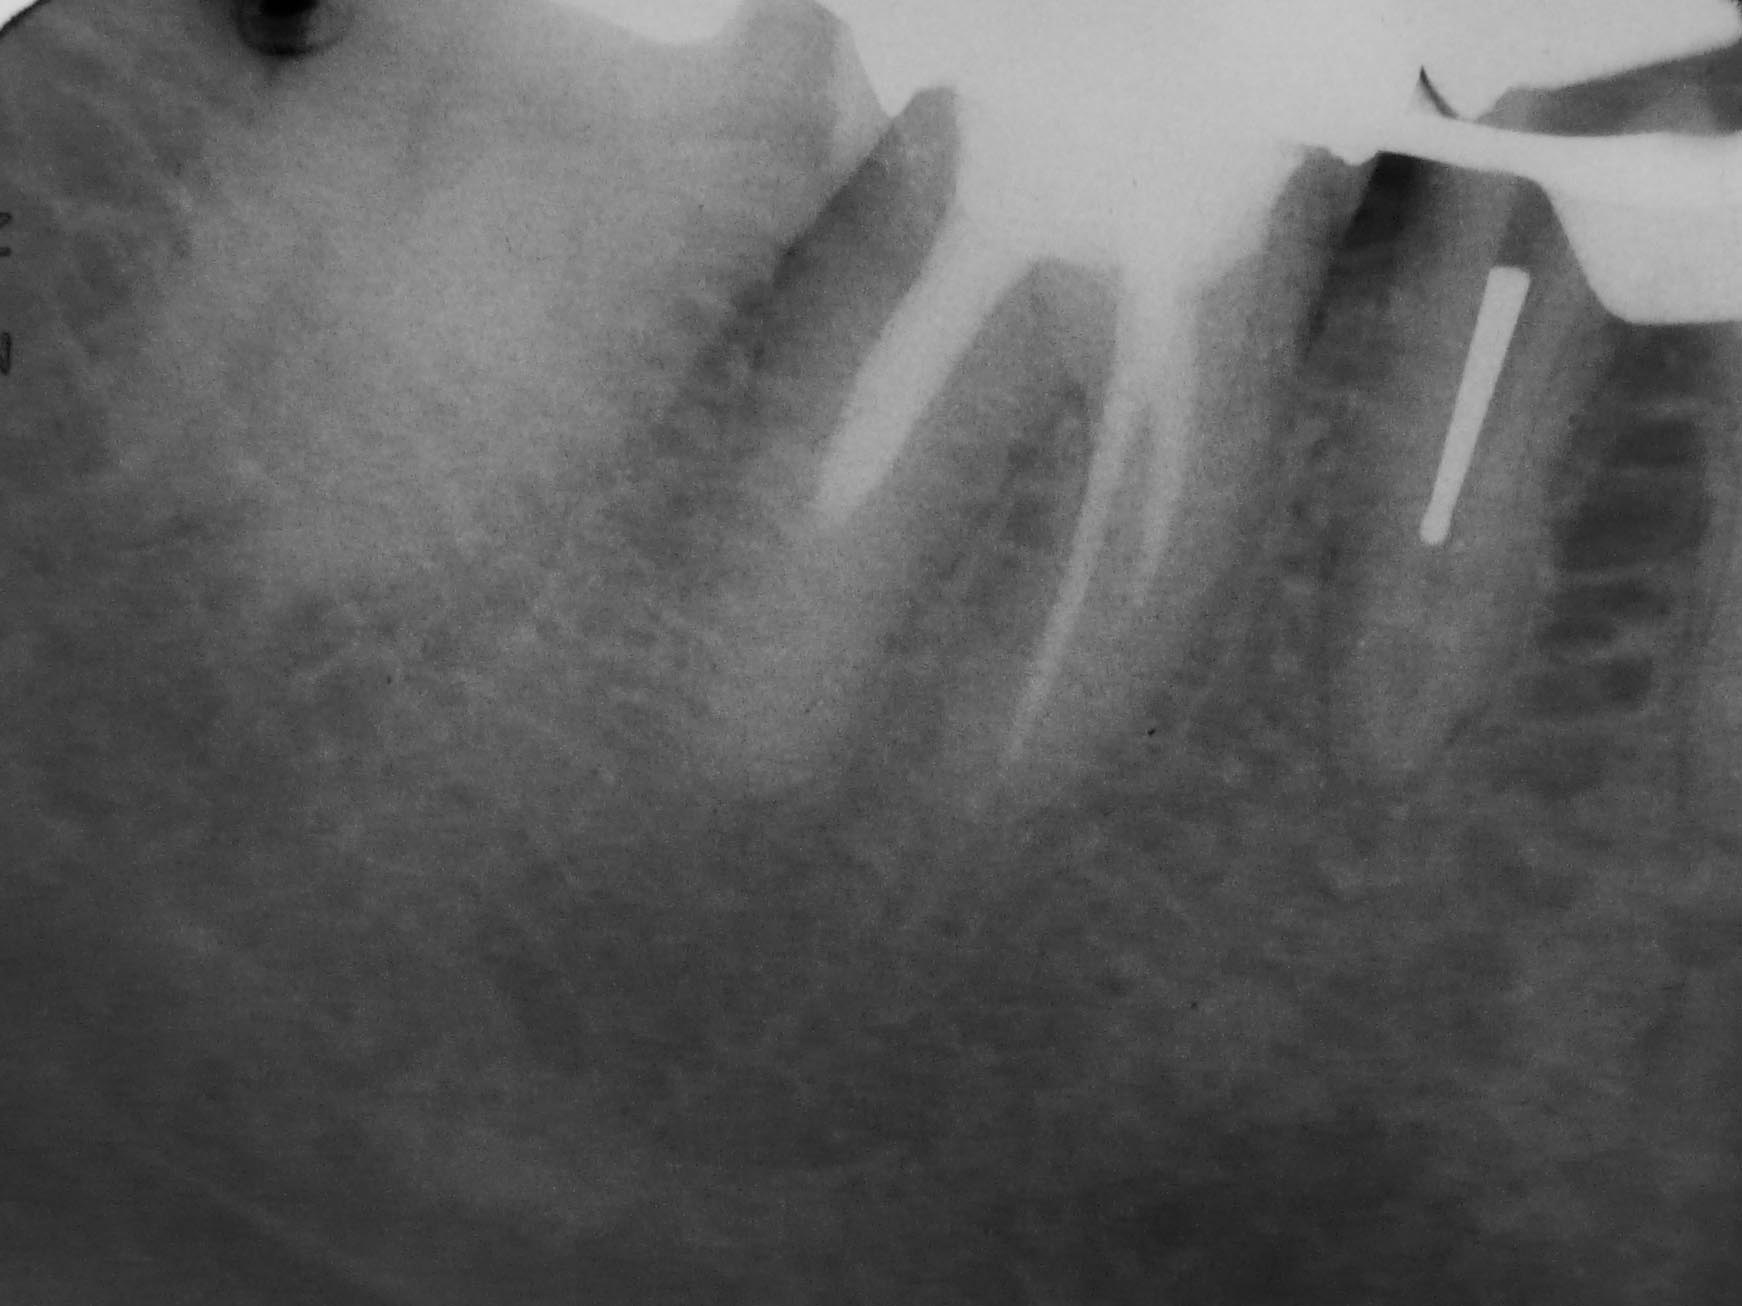

Rätselbild-3 Veröffentlicht 31. August 2009 am 1742 × 1306 in Shit happens: Das Rätselbild – Die Auflösung